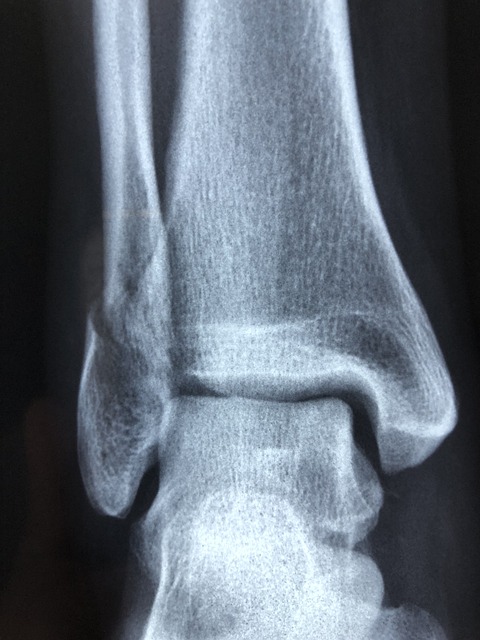

측 방향 검사

검사 목적

측면 상에서 먼 쪽 종아리뼈와 정강뼈, 발목관절, 목말뼈와 발꿈치뼈를 관찰할 수 있습니다.

검사방법

촬영 쪽을 밑으로 하여 옆으로 눕히고, 머리에 베개를 받쳐 편안한 자세로 합니다.

촬영 쪽 무릎을 약 45° 기울이고, 반대쪽 다리는 촬영 쪽 다리 뒤에 놓는다. 골반부를 차폐하여 생식샘을 보호합니다.

내·외 측 방향 촬영

발목관절을 상 수용체 중앙에 두고 상 수용체 장축과 다리 장축을 일치시키고, 필요에 따라 무릎아래 지지물을 놓고, 다리와 발은 바른 측면 자세로 합니다.

종아리뼈 먼쪽부분의 바깥쪽 복사는 정강뼈 먼쪽부분 안쪽보다 약 15도에서 20도 뒤에 위치하고 발을 뒤로 당겨서 발이 다리와 직각 되게 하고, 환자는 가능한 참을 수 있도록 하여 바른 측면 자세를 유지해야 합니다.

중심 X선은 안쪽복사를 통해 상 수용체 중앙에 수직으로 입사합니다.

X선관 초점-영상 면 사이 거리는 약 100cm로 촬영합니다.

조사 범위 범위는 정강뼈, 종아리뼈 먼쪽부분과 발허리뼈 중간 부분과 연부조직이 포함되어야 합니다.

영상의 평가

발목관절 중앙이 상 수용체 중앙에 나타나야 하며, 거퇴관절 윗부분 관절 사이가 균일하게 분리되어 나타나야 합니다.

바깥쪽 복사와 종아리뼈 먼쪽부분은 정강뼈 뒤쪽 1/2 또는 1/3, 목말뼈 뒤쪽 반과 겹쳐 나타나며, 목말뼈와 발꿈치뼈 전체가 보이고 인접한 발목뼈가 보여야 합니다.

적절한 노출로 종아리뼈 먼쪽부분의 윤곽과 연부조직이 선명하게 관찰되고, 모든 뼈의 미세구조와 면이 선명하게 보여야 합니다.